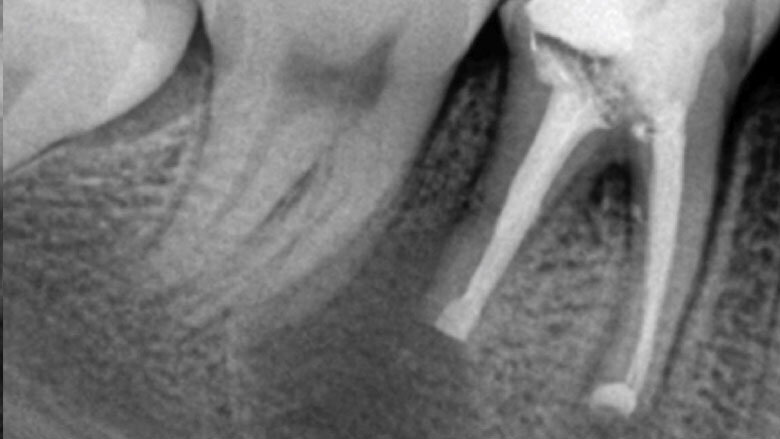

Apicectomía del diente 46.

Se debe proteger al máximo la integridad de las células del ligamento periodontal, para que se dé una buena cicatrización de las mismas durante la reimplantación. La manera de protegerlas es usar un tiempo extraoral extra corto, no mayor a 15 minutos y entre más bajo mejor. Después de la extracción del diente, las raíces se examinan en busca de fracturas, conductos adicionales o istmo y cualquier característica anatómica adicional que requiera sellarse para evitar la salida de bacterias al exterior. La inspección de la raíz se realiza mejor con la ayuda de un microscopio dental6. Dado que no se necesita una osteotomía, la reimplantación no produce la pérdida de hueso vestibular o palatino para llegar al ápice radicular. Esto facilita la curación postoperatoria al no sacrificar hueso sano para llegar al sitio donde se ubica el ápice radicular. Durante la apicectomía convencional, el campo de visión está limitado por la osteotomía y las estructuras adyacentes, como el arco cigomático y el tejido de la mejilla. Sostener un diente extraído permite un acceso total para inspeccionar toda la superficie de la raíz (4). La manipulación de instrumentos microquirúrgicos y ultrasonidos es más fácil con el diente fuera de la boca. Una reducción del tiempo extra oral es imprescindible en la prevención de la anquilosis, la reabsorción radicular y para promover el proceso de curación peri-radicular mediante la prevención del daño y deshidratación de las células periodontales7. Es grandioso darse cuenta cómo los pacientes quedan altamente agradecidos por conservar sus dientes. Es el endodoncista o el odontólogo el que decide desahuciar dientes que pueden salvarse, y si como especialistas nos entrenamos en técnicas avanzadas, más dientes podremos salvar de la pérdida. En muchos casos, factores económicos impiden que un paciente que pierde los dientes, pueda reemplazarlos, y la falta de dientes está relacionado con problemas gastrointestinales, con cáncer de estomago, cáncer colon rectal e inclusive con Alzheimer8.9. Debemos de verdad aumentar el valor que le damos a los dientes naturales; si fuéramos a perder un riñón, ¿no agotaríamos todos los recursos por salvarlo? Nuestra meta debe ser lograr que nuestros pacientes lleguen con sus dientes naturales hasta la vejez.